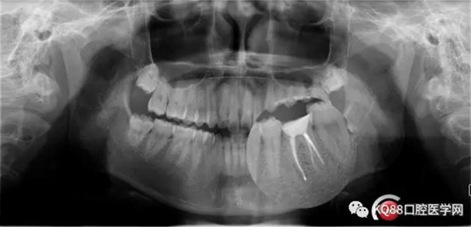

第五步:充填完成,ZOE暫時觀察。

9.png

10.png

充填完成,暫時觀察一周。下一步做牙冠延長,近遠(yuǎn)中打纖維樁,全冠或嵌體修復(fù)。